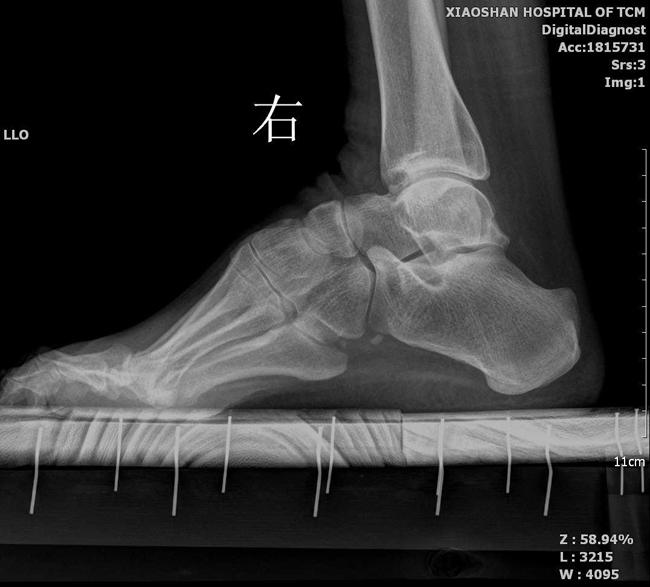

首先,详细而完整的病史对了解病情及进展情况非常重要,对于高弓足病因的明确,需要进行完善的神经学检查以确定或排除神经系统疾病,包括下肢肌力、腱反射、感觉、运动以及神经电生理特征等;其次是进行临床评估,包括评估患者站姿、足踝部外形、足跟及足趾行走情况、足下垂程度、跖屈受限程度、足旋转程度、踝关节被动活动度等;第三则是影像学检查,主要包括标准足踝部X线片、负重足正侧位片和木块位片,对于骨骼严重畸形改变的患者需要行螺旋CT及重建来了解骨骼变性的严重程度和累及范围,对于需要行肌腱移位或软组织重建手术的患者,MRI检查可用于评估软组织情况。